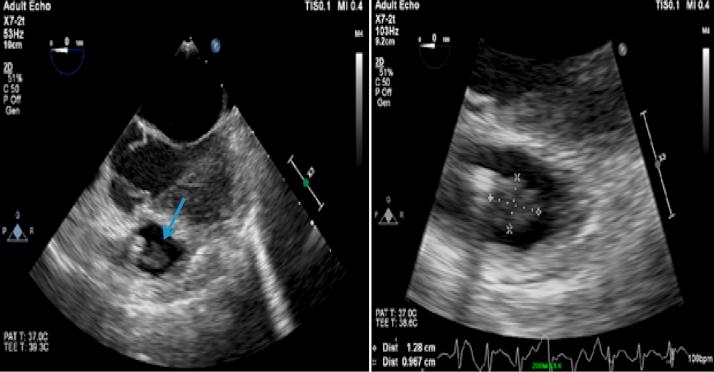

Treating an infected transcatheter pacemaker system via percutaneous extraction.

HeartRhythm Case Rep. 2016 May 10;2(4):360-362. doi: 10.1016/j.hrcr.2016.04.006. eCollection 2016 Jul.